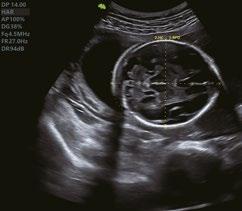

Fetaler Nasenknochen

Babygesicht 3D